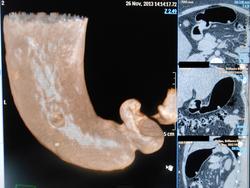

Больная В. 38 лет Диагноз: «Карциноид тела желудка малых размеров 11х9мм» (подтверждён гистологически).

2.-Компьютерная пневмогастротомограмма

3.-2D -изображения с раздуванием желудка воздухом

4.-3D-реконструкция раздутого воздухом желудка (вид сзади)

5.-Виртуальная КТ-гастроскопия